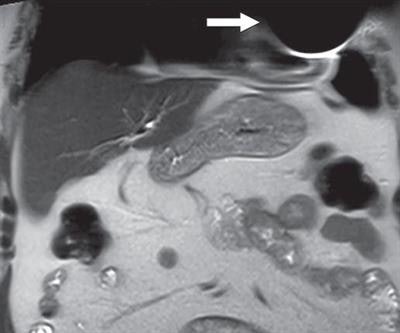

In the end, all MR images were of diagnostic quality for the targeted clinical application. Three studies (4%) had artifacts in the chest wall, which were due to the presence of the device's pulse generator in the field-of-view, and limited evaluation of tissue adjacent to the device. All other MRI scans were artifact-free.